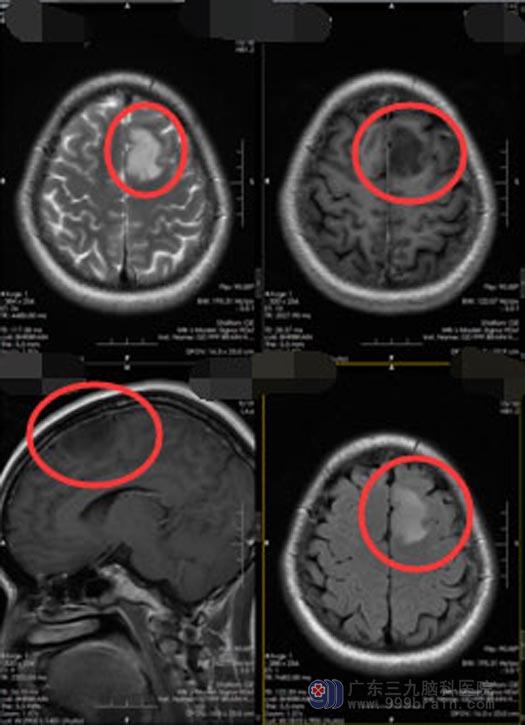

小陈在2个月前右侧肢体突然发生抽搐,发作时两眼直视,呼叫无反应,持续有2-3分钟,小陈及家人都认为是过度劳累引起的。直到抽搐再次发作,才去当地医院就诊,头颅MR检查显示:“左额叶占位性病变,考虑低级别胶质瘤”。

入院后,进一步头颅MR检查提示:左侧额叶占位性病变,考虑为弥漫性星型细胞瘤可能性。额叶是与躯体运动、语言、发音及高级思维有关,此区为精神和智力的功能区,与精神状态、记忆力、判断力和理解力等有密切关系,手术稍有不慎,容易引起肢体瘫痪,失语等。小陈的肿瘤正好长在功能区,同时伴有癫痫发作,比较棘手,医院副院长、神经外五科主任鲁明带领团队经过缜密的术前讨论,决定采取术中唤醒麻醉为她切除功能区肿瘤,并术中用脑电监测癫痫灶。

术中小陈唤醒成功,配合默契,荧光显微镜下全切肿瘤,肢体运动功能及语言功能保护好,术后未出现神经功能障碍,也没有出现癫痫发作,复查头颅mr肿瘤完全切除,已康复出院。

手术前